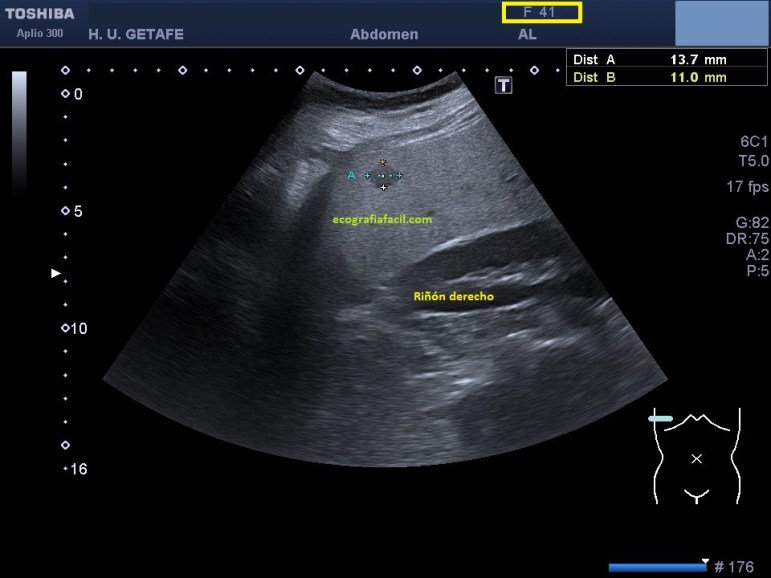

La LOE fue estudiada de manera protocolaria, haciendo medidas y aplicándose el Doppler, en este caso el modo angio o doppler power.

Finalmente la Radióloga informó la lesión como HNF aún siendo marcadamente hipoecogénica, si te fijas bien en las imágenes, sobre todo en la imagen 3, donde se observa el riñón derecho, verás que existe una marcada hiperecogenicidad hepática en relación con el riñón derecho, que como muy bien sabes, deben ser isoecogénicos.

La paciente por tanto padece una esteatosis hepática, la lesión es hipoecogénica con respecto al parénquima hepático infiltrado de grasa, pero isoecogénica con el patrón ecográfico de la corteza renal, donde quiero ir a parar es a que la LOE de HNF sería isoecogénica con el parénquima hepático si eventualmente, éste, estuviese sano, es decir, si no estuviese infiltrado de grasa.

No quiero acabar sin pedirte que cuando hagas una ecografía abdominal, a la hora de estudiar el lóbulo hepático derecho, pongamos al paciente en decúbito lateral izquierdo, esta lesión era tan excéntrica que sin haber movilizado a la paciente, hubiese sido imposible visualizarla, era además muy subcostal, de facto, parte del estudio se hace intercostal.